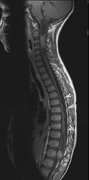

first used in 1936.166 The first major clinical criteria for the syndrome were proposed in 1964.167 The main manifestations of von Hippel-Linau syndrome are: histologically similar hemangiomas of the retina and CNS, renal cysts, renal cell carcinomas, pancreatic cysts, pheochromocytomas, and endolymphatic sac tumors.13 EPIDEMIOLOGY The prevalence of VHL syndrome is about 1 in 35,000 to 40,000.168 It is autosomal dominant with greater than 95% penetrance by age 60 years.169 Its expression, even within the same family, may be quite variable, especially for renal disease and pheochromocytoma.170,171 SYSTEMIC FEATURES Cutaneous Findings Cutaneous findings are not part of the diagnostic criteria for VHL syndrome. Neurologic Findings CNS hemangiomas are the most common tumor of VHL, affecting 60% to 80%, with a predilection for the cerebellum and spinal chord. An enlarging cystic component is a frequent finding in symptomatic tumors. Patients typically present in their early 30s; headaches or neck pain in affected individuals should not be ignored.172,173 On microscopy, CNS hemangiomas resemble retinal capillary hemangiomas. Their malignant potential is low.174 The treatment is surgical (Fig. 17, A and B).13 Endolymphatic sac cystadenomas are a sensitive marker of VHL. Patients may present with hearing loss, tinnitus, disequilibrium or facial nerve palsy.175,176 Visceral Findings KIDNEY. Renal cysts are often asymptomatic and do not require treatment. However, complex cysts may carry a risk for malignant transformation. Renal carcinoma affects about a third of patients. Patients typically present in their late 30s. These tumors may be completely asymptomatic, underscoring the necessity for ultrasound screening.13,177 ADRENALS. Pheochromocytomas are benign neural crest tumors of the adrenal medulla (chromaffin cell derived) and probably affect 10% to 20% of patients. Mean age at diagnosis is at about 30 years of age. Pheochromocytomas may be multiple and bilateral. They are catecholamine-secreting tumors that classically produce severe hypertension and anxiety attacks, but they may also be asymptomaic.178 The National Cancer Institute classification of VHL syndrome is in part based on the absence (type I) or presence (type II) of pheochromocytoma (Table 5).171